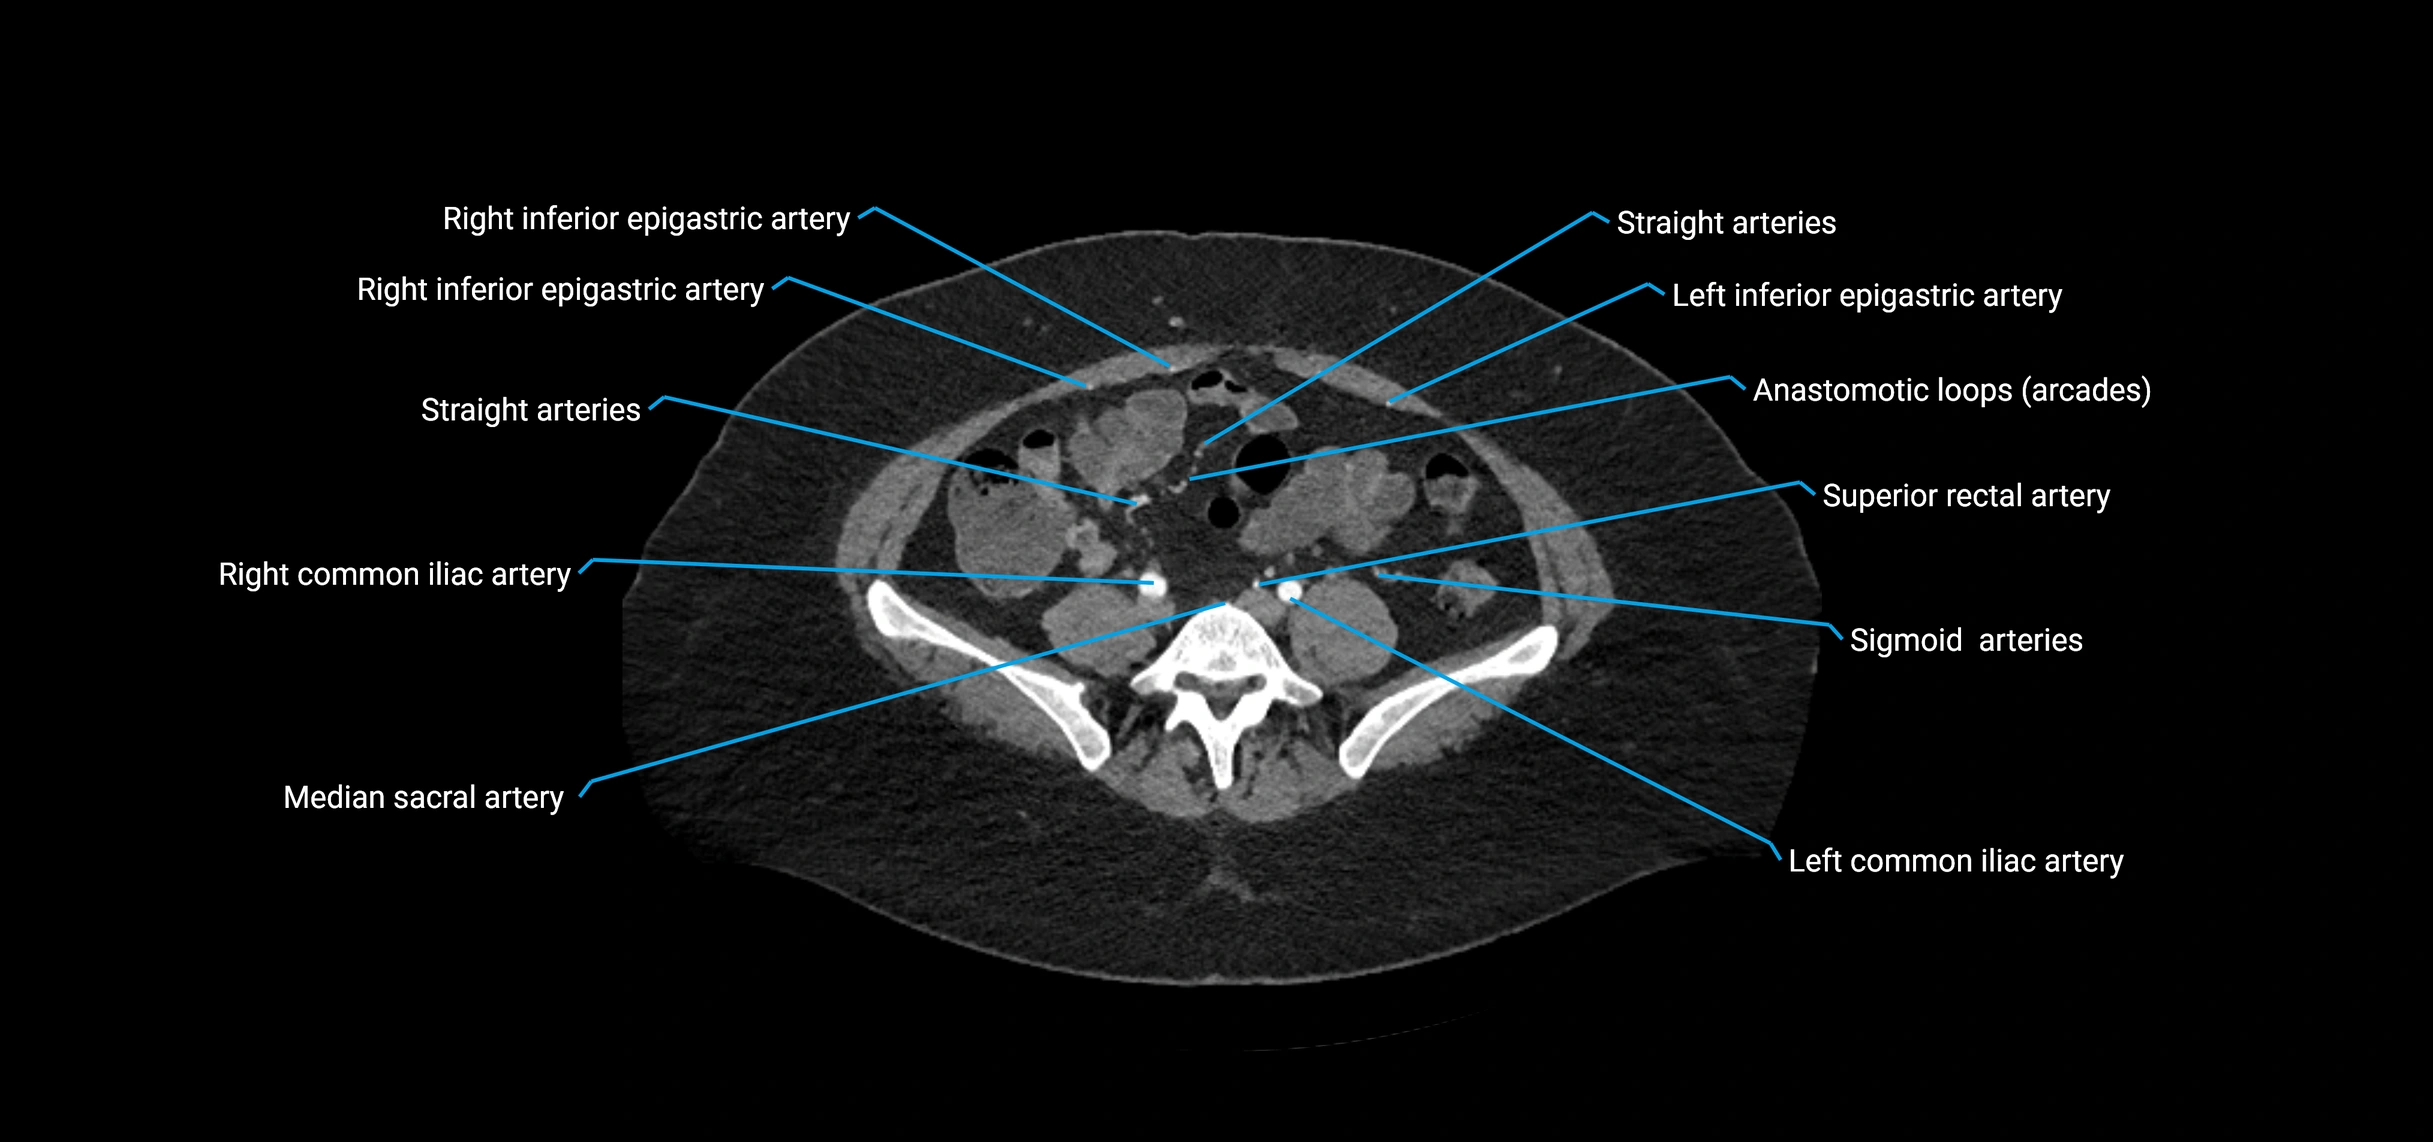

Contrast-enhanced CT (CTA):

• Gold standard for abdominal aortic imaging

• Provides excellent detail of lumen, wall, aneurysm, thrombus, and branch vessels

• Multiplanar and 3D reconstructions help in aneurysm measurement, stent graft planning, and dissection evaluation

• Detects acute rupture, traumatic injury, or occlusion with high sensitivity